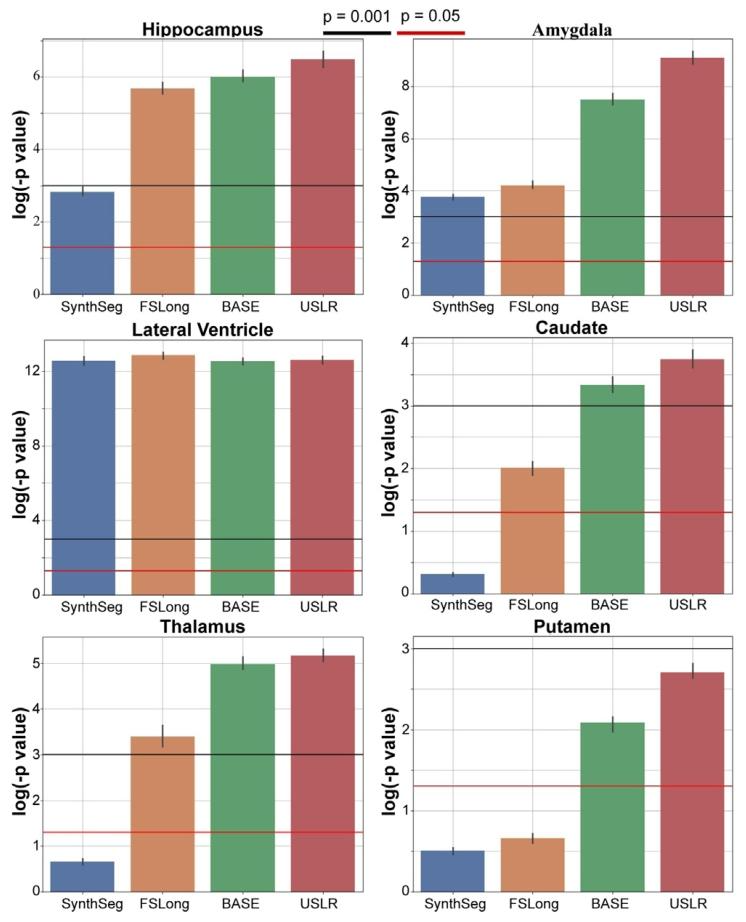

Fig. 11. Linear mixed-effects model with random intercept and slope. We plot the𝑙𝑜𝑔(𝑝* − 𝑣𝑎𝑙𝑢𝑒) of a contrast comparing time evolution between cognitively normalsubjects and AD subjects. The bars represent the median value of 𝑁 = 1000 bootstrapsample. We compare three different segmentation methods: cross-sectional SynthSeg(blue), the longitudinal stream of Freesurfer (dark orange) and our USLR framework(green). Red line represents a 𝑝-value of 5 ⋅ 10−2 and the black line a 𝑝-value of 1 ⋅ 10−3 .

图11 带有随机截距和斜率的线性混合效应模型。图中绘制了对比认知正常受试者与阿尔茨海默病(AD)受试者时间演变差异的𝑙𝑜𝑔(𝑝值)。误差条代表𝑁=1000次bootstrap抽样的中位数。我们比较了三种不同的分割方法:横断面SynthSeg(蓝色)、FreeSurfer纵向流程(深橙色)以及我们的USLR框架(绿色)。红色线代表𝑝值为5×10⁻²,黑色线代表𝑝值为1×10⁻³。